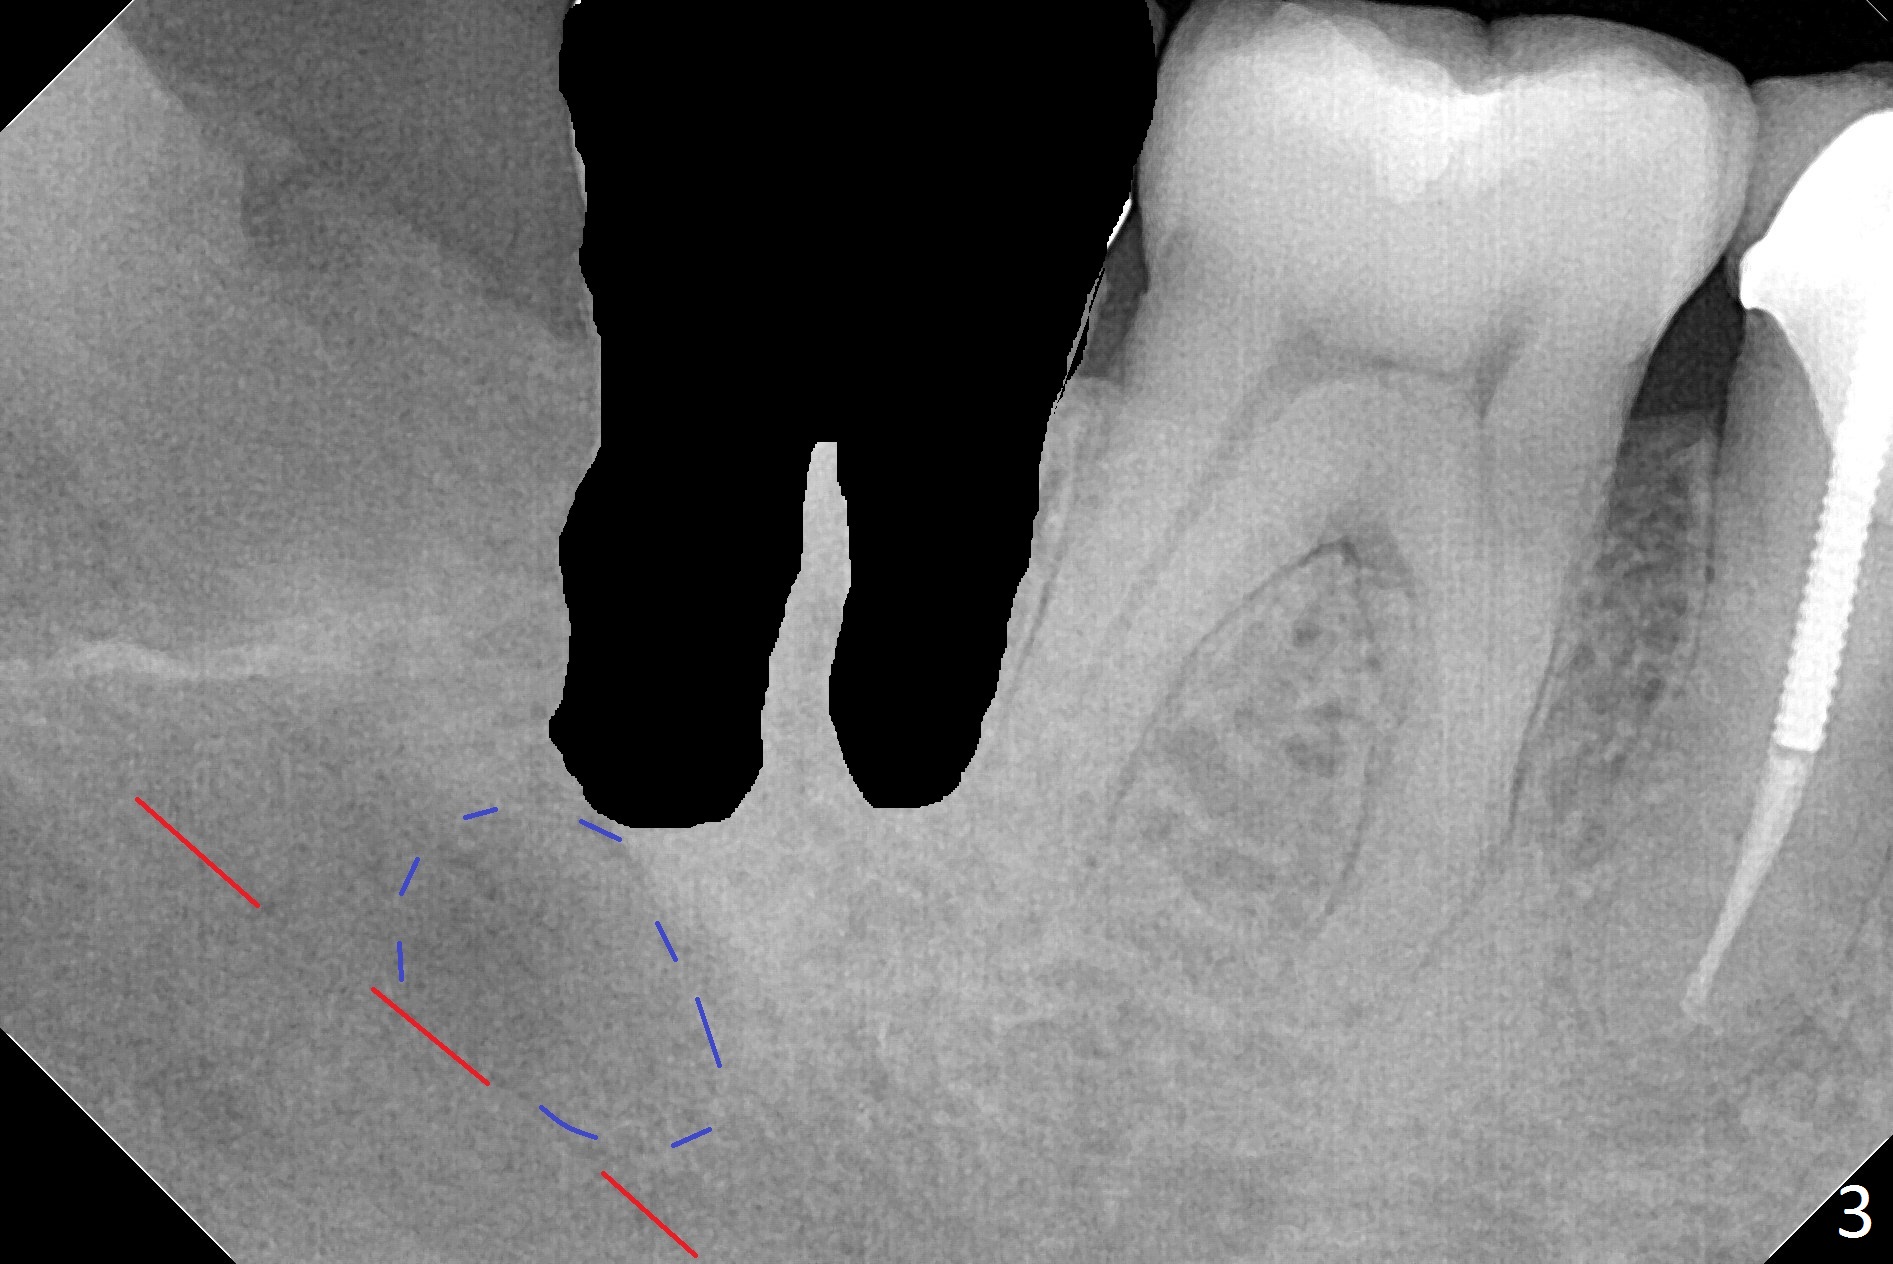

A 45-year-old woman presents to clinic with swelling and pain from the lower right posterior region. The tooth #32 is fully bony impacted. The distolingual gingiva of #31 is erythematous with deep pocket. The tooth is sensitive to percussion. Preop panoramic X-ray shows a radiolucent lesion between #31 and #32 (Fig.1 blue dashed line). Initial impression is infection from #32. Extraction of the latter turns out to be difficult. Purulent discharge is coming from underneath the coronal portion of the tooth. Curettage of the radiolucent lesion leads to hemorrhage. The curettage is not aggressive because of the underlying Inferior Alveolar Canal (red dashed line). Following copious irrigation, a 10x20 mm Osteogen plug is inserted into the socket with incision closure. Postop PA reveals that the roots the teeth #31 and 30 approximate to each other (Fig.2 R). In case the tooth #31 needs to be removed (Fig.3 black area), osteotomy for immediate implant will be established in the middle of the septal stump (Fig.5 red arrow) after removal of the coronal septum (Fig.4). CBCT may be necessary for determination of the osteotomy depth.